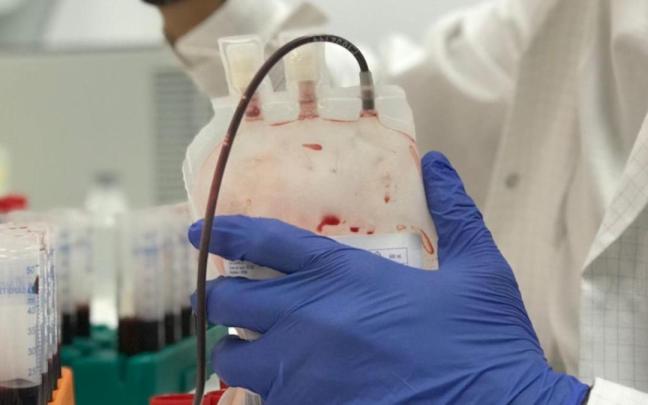

Un nuevo método permite diagnosticar el cáncer de mama con una gota de sangre

Esta nueva técnica no invasiva consiste en el análisis del ADN mediante secuenciación masiva, lo que permite la detección de presencia del ADN liberado por las células tumorales a la sangre

Investigadores del Cima y de la Clínica Universidad de Navarra logran revertir una causa del cáncer de la sangre asociado a la edad

Han identificado una proteína alterada en los pacientes con síndrome mielodisplásico que, al inhibirla, restaura la funcionalidad de las células sanguíneas implicadas en la enfermedad